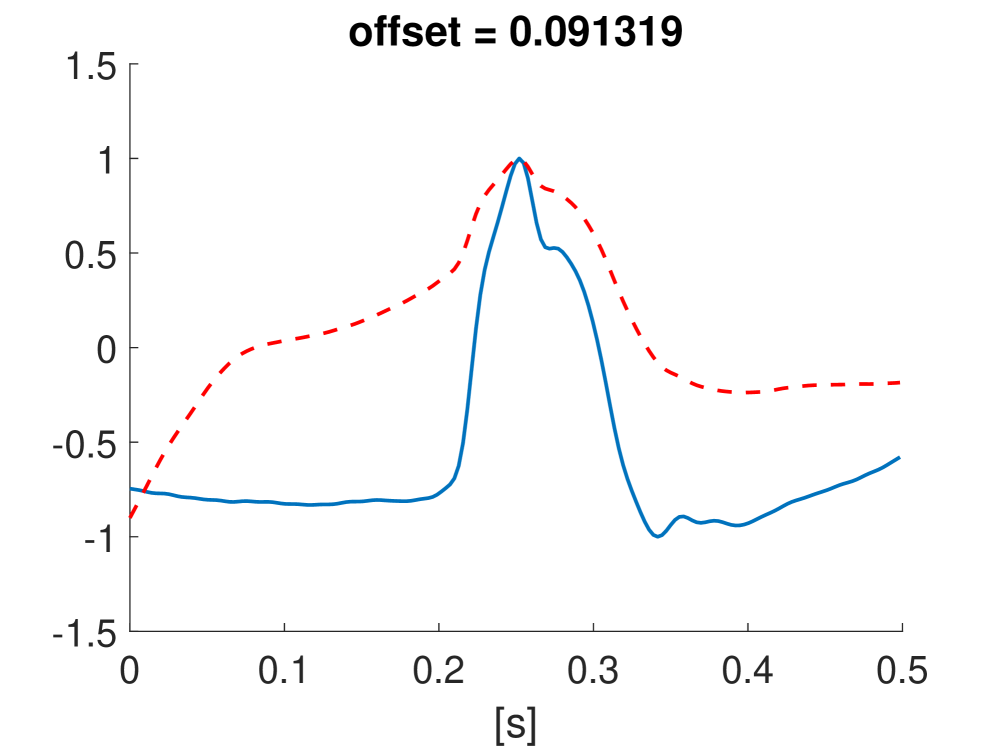

Fig. 10 shows the result in input space of moving along the first principal components in the latent feature space. As original base point we take a normal beat signal, i.e. corresponding to a hidden unit on the bottom right of Fig. 9(a). The smooth transition between the beat patterns allows for interpretation of the first principal components. This allows a clinical expert to understand on what basis the paced beats are separated by the principal components and if this basis has a physiological meaning. In order to investigate the separated region of the latent space at the top of Fig. 9(b) we start from a paced beat pattern and vary along the third principal component. This allows us to see which sort of heartbeat patterns are responsible for this specific distribution in the latent space.